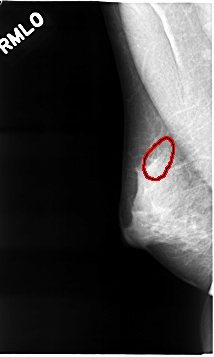

C_0036_1.RIGHT_MLO

FILE: C_0036_1.RIGHT_MLO.OVERLAY

TOTAL_ABNORMALITIES 1

ABNORMALITY 1

LESION_TYPE CALCIFICATION TYPE PUNCTATE DISTRIBUTION CLUSTERED

ASSESSMENT 4

SUBTLETY 4

PATHOLOGY MALIGNANT

TOTAL_OUTLINES 1

BOUNDARY